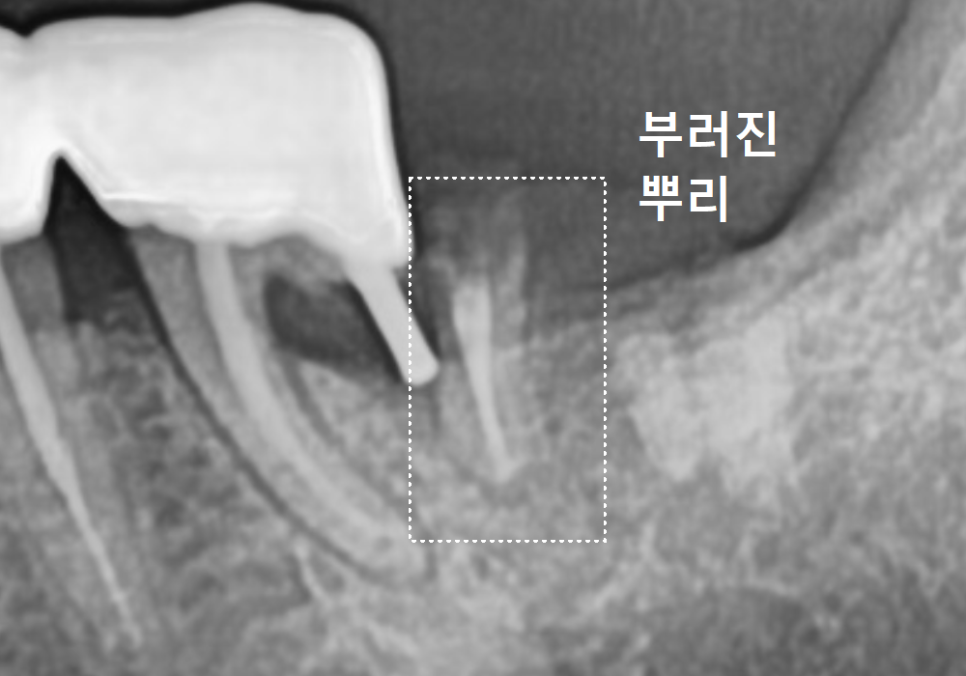

[사례 1] 뼈가 녹아 기다림이 필요했던

지연식립 케이스

강동구 임플란트 기간, 사람마다 왜 다를까? 즉시식립과 지연식립의 결정적 차이

먼저 지연식립을 진행했던

환자분의 사진을 함께 살펴볼까요?

오른쪽 아래 맨 끝 어금니(#47) 부위를 보시면

뿌리 끝부분이 까맣게 보이죠.

뿌리끝에 염증이 생겨서 이 염증으로 인해

뼈가 녹아 까맣게 보이는데요~

잇몸뼈는 밀도가 높을수록

하얗게 나타나고,

염증으로 인해 뼈가 녹아

밀도가 낮아지면 이렇게 까맣게 보이게 됩니다.